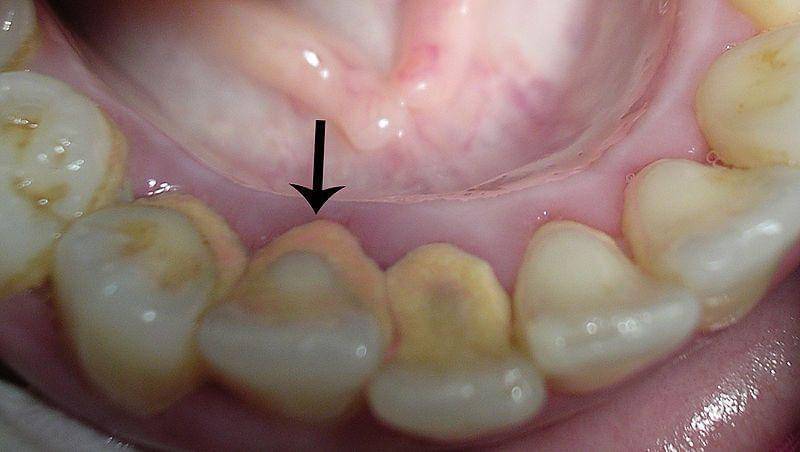

Karang gigi atau kalkulus gigi adalah endapan keras dan terkalsifikasi yang membentuk dan melapisi gigi dan gusi. Jika plak gigi tidak dihilangkan secara teratur, seperti dengan menyikat gigi dan flossing, plak lama-lama akan mengeras dan menjadi karang gigi.

Penumpukan karang gigi dapat menyulitkan kamu menyikat gigi dan membersihkan gigi dengan benar, sehingga menyebabkan gigi berlubang, penyakit gusi, dan bau mulut.

Plak dan karang gigi sebagian besar menumpuk ketika kamu tidak menyikat gigi atau membersihkan gigi dengan benang secara efektif. Titik yang terlewatkan atau gerakan yang salah menjadi penyebab utama kuman menumpuk, terutama di belakang gigi.

Oleh karena itu, jika kamu menyikat atau membersihkan gigi dengan agresif atau tidak tepat, ini bisa menyebabkan sebagian dari akumulasi ini terkelupas dan rontok.

Jadi, ada kemungkinan karang gigi pecah saat melakukan flossing atau kamu mungkin melihat bagian belakang bawah gigi depan terkelupas saat memakan sesuatu yang keras.